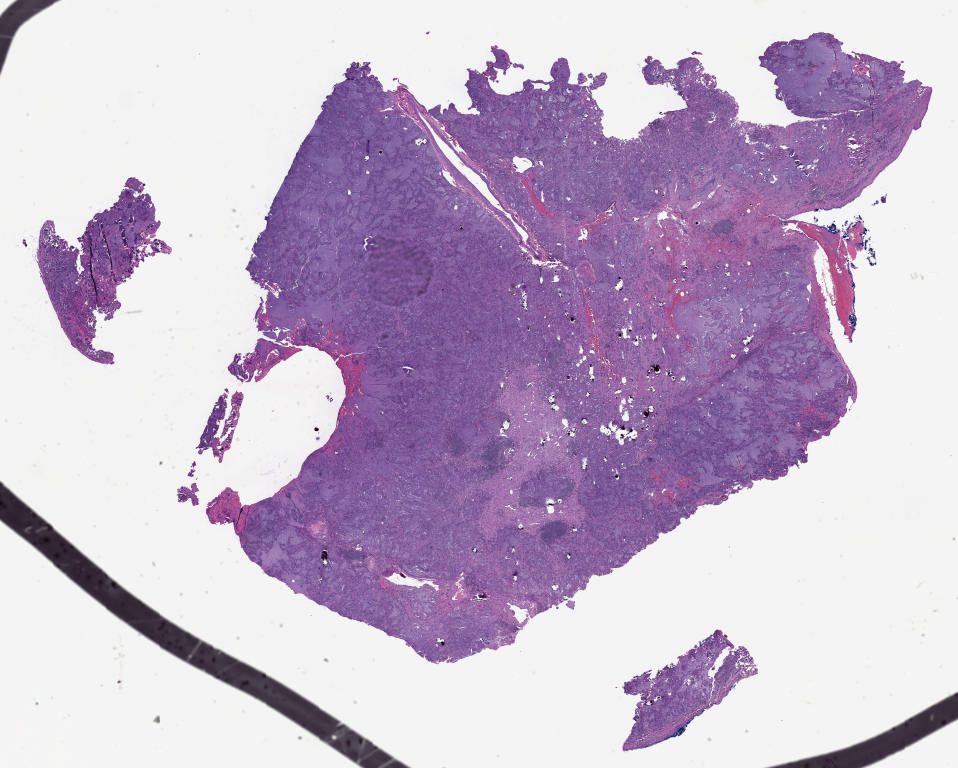

Patient 1.svs

45816

x

34469

@

20X